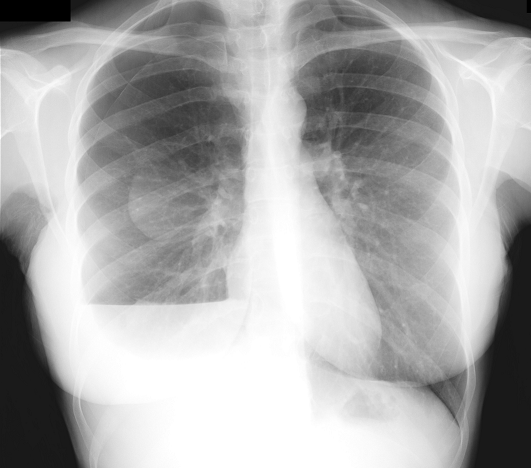

Recurrent spontaneous pneumothorax in young woman: catamenial pneumothorax

A 31-old-year woman came to hospital for dyspnea. She was a non smoker patient and had no history of previous pneumothorax. She was under gynecologic study for having troubles to get pregnant. On physical examination she had tachypnea and right chest hypoventilation. Blood test showed slight leukocytosis and chest x-ray revealed a right hemopneumothorax. A chest tube was placed and few days later she required surgery for persistent air leak. Apical blebs were found and resected by video thoracoscopy. Gynecologic studies were completed and she was diagnosed of pelvic endometriosis and treated by bilateral salpingectomy and left partial oophorectomy with confirmed endometriosis on pathology. She had three more episodes of smaller right pneumothorax in relation with menses. On the last episode she underwent surgery to perform a pleurodesis. Small tissue implants were resected, which were negative for endometriosis. One year later she has had no more episodes and she is actually under in vitro fertilization procedures to get pregnant. Catamenial pneumothorax is related with up to 3% of spontaneous pneumothorax in women, and should be considered as differential diagnosis, especially in those with troubles to get pregnant.